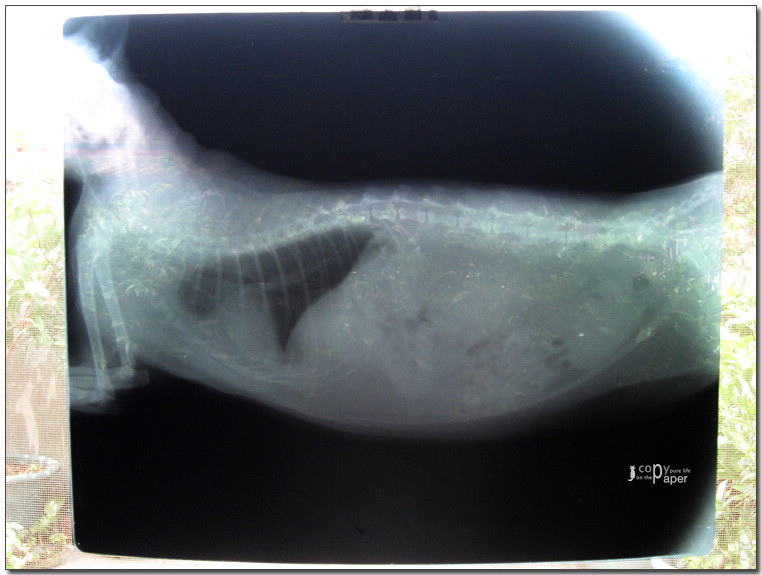

照了X光,

做了超音波,

體重6.4公斤(明明瘦瘦的,怎麼那麼重?),

好像沒什麼大礙,

打了2針,

又拿了二星期的藥,

買了化毛膏。